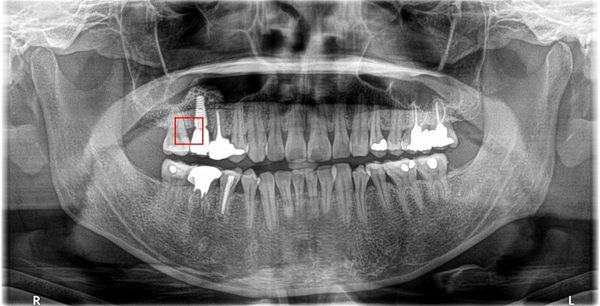

因為長不出來的智齒位於口腔最後方不易清潔的位置,殘留的食物殘渣容易被細菌所利用來侵害人體。

在平時,細菌造成的慢性感染會使牙齦發炎,容易流血,出現骨吸收、蛀牙及牙痛,最後因牙周病的牙齒鬆動或牙髓壞死而拔牙。這時隔壁有用的第二大臼齒往往也會受到波及而造成不等程度的傷害,甚至拔牙,這也是最可惜的地方。

空間不足時其牙胚可能會吸收前方第二大臼齒之牙根使其強度減低,影響其功能。異位或萌出不全的智齒亦往往會對正常咬合造成乾擾,牽動下頜骨之肌肉必須常常做出異常收縮來避開此干擾,而使得肌肉及關節容易有發炎疼痛之現象。